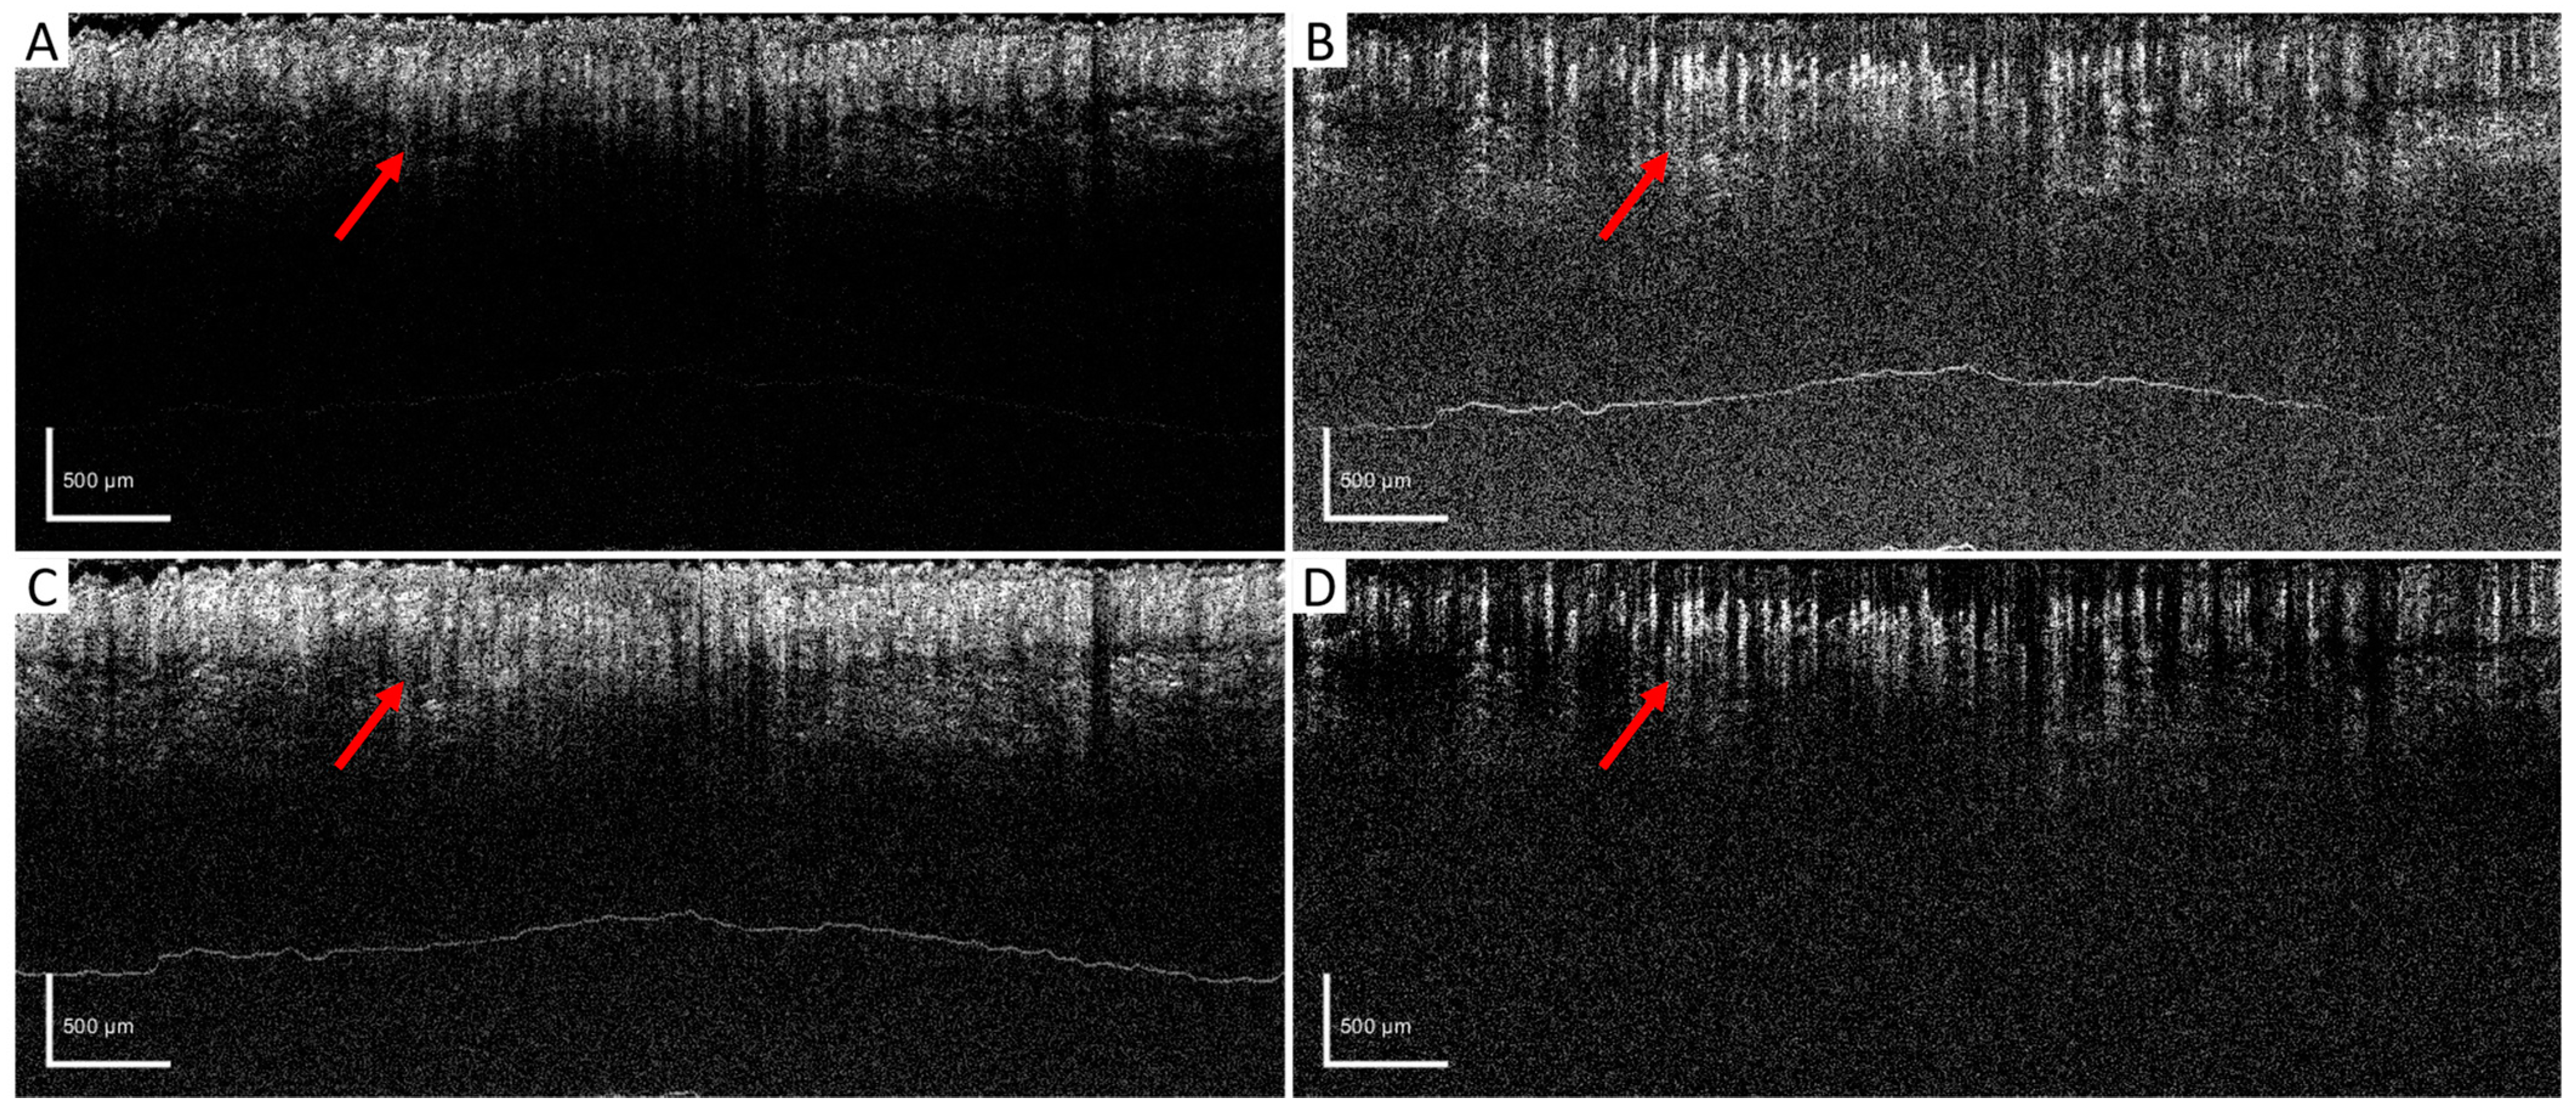

2. Materials and Methods

3. Results

3.3. In Vivo Results Comparisons